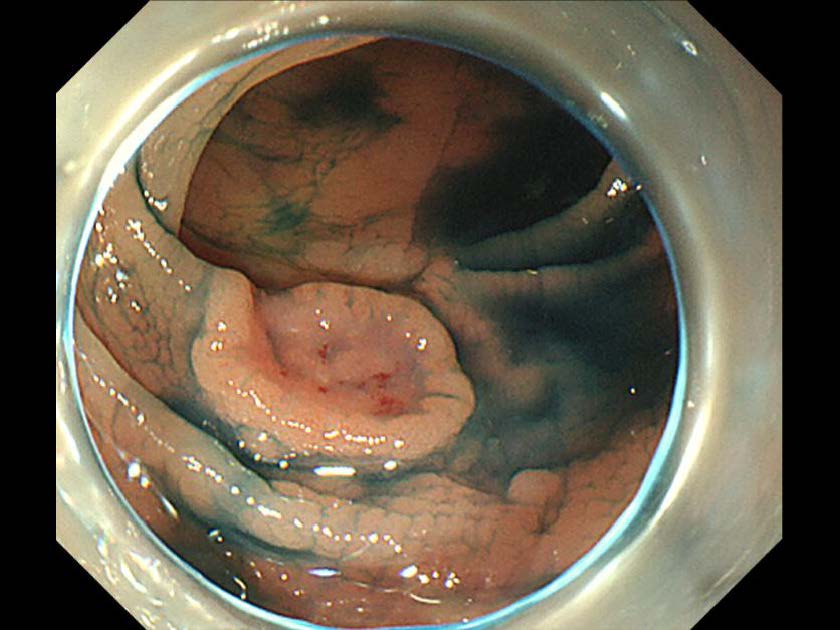

消化管Mapping~大腸~ 2021.10.27

消化管Mapping~大腸~

消化管Mapping

全ページPDFのダウンロードはこちら